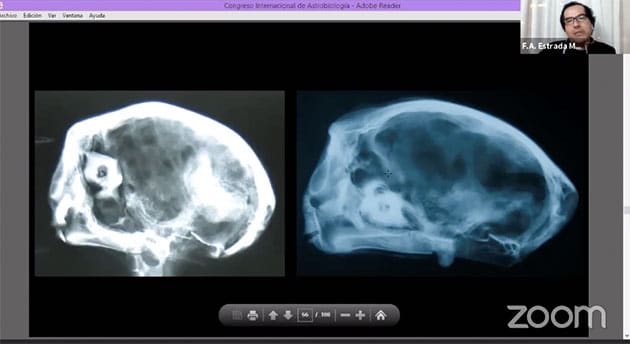

Die Röntgenaufnahmen des Schädels (Abb. 17, 18, 19 u. 20) weisen auch diesen ursprünglich als Tierschädel aus. Allerdings wurde dieser Tierschädel stark aber erfinderisch und ideenreich bearbeitet.

Tatsächlich kann anhand bekannter Schädelmerkmale gezeigt werden, dass das frontale „Gesicht“ der Mumie auf und aus der Rückseite des Schädel aufgebaut wurde und die eigentliche Schnauze des Tierschädels hierzu entfernt wurde. Ersichtlich wird dies zunächst durch den sich schon anhand der Röntgenaufnahmen (Abb. 17-20) abzeichnenden Umstand, dass der Mumienschädel äußerlich zwar Augen und vermeintliche Augenhöhlen zu besitzen scheint, diese im Schädel selbst aber nicht vorhanden sind.

Anhand verschiedener Merkmale bekannter Tierschädel (zum Vergleich werden Schädel eines Hundes und einer Katze verwendet) können die Forschenden der UNICA den Umstand, dass hier ein umgedrehter und stark bearbeiteter Schädel zu einem Alien-artigen Mumien-Schädel samt falschem Gesicht umgearbeitet wurde, anschaulich bebildert nachweisen. Der einzige Schädelausgang des Mumienkopfes, durch den eigentlich das Rückenmark mit dem Gehirn verbunden wäre, stellt in Wirklichkeit einen Teil des Oberkiefers des Schädels eines Vierbeiners (die genaue Art wurde bislang nicht bestimmt) dar (s. Abb. 22) und nicht dem sog. großen Hinterhauptsloch (Foramen magnum).

Auch ein Vergleich von Josefinas Schädel (s. Abb. 44, 45, 46 l.) mit vorigen Schädeln (Abb. 44. 45, 46 r.) zeigt die Ähnlichkeiten und offenbart erneut, dass auch hier der umgedrehte Schädel eines Vierbeiners verwendet wurde. Auf den Schädeln sind linienförmige Grate zu erkennen (Abb. 47), an denen in der Natur bei den Tieren Muskeln ansetzten – Muskeln, für die es bei Josefina (und den anderen Mumienschädeln) aber keine Anzeichen gibt.